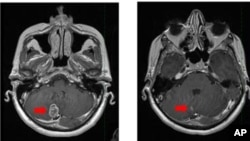

دانشمندان اسرائیلی به روش جدیدی برای درمان اوتیسم و پارکینسون دست یافتند

پژوهشگران موسسه فناوری Technion-Israel اعلام‌کردند با کشف دقیق چگونگی عملکرد مغز در حرکت و تعادل توانسته‌اند به درمان کامل بیماری‌هایی نظیر اوتیسم و پارکینسون نزدیک‌تر شوند.

این دانشمندان دریافتند که محاسبات مغزی، نه‌تنها در تعامل بین سلول‌های عصبی، بلکه در درون هر نورون نیز به‌طور جداگانه انجام می‌شود.(‌متن اصلی گزارش خبری را اینجا بخوانید )

پروفسور جکی شیلر، از دانشکده پزشکی موسسه فناوری Technion-Israel در شهر حیفا و تیم او، کشف کردند که هریک از سلول‌های میکروسکوپی عصبی، فراتر از یک سوئیچ ساده، مانند یک ماشین محاسبه پیچیده یا یک کامپیوتر کوچک بیولوژیک عمل می‌کنند.

کشف محققان اسرائیلی، نه‌ تنها این ظرفیت را دارد که «درک انسان را از نحوه عملکرد مغز، بالا ببرد»، بلکه می‌تواند امید و ‌‌دانسته‌ها را در مورد «درمان شرایط عصبی جدی» در بیماری پارکینسون و اوتیسم، نیز افزایش دهد.

در بیماری اوتیسم، ممکن است «تحریک‌پذیری شاخه‌های دندریتیک» تغییر کرده و عوارض این بیماری را گسترش دهد اما با درکی تازه که از شیوه عملکرد نورون‌ها به‌دست آمده، مسیرهای تحقیقاتی جدیدی برای درمان بهتر این بیماری و بیماری‌های دیگر باز شده‌ است.